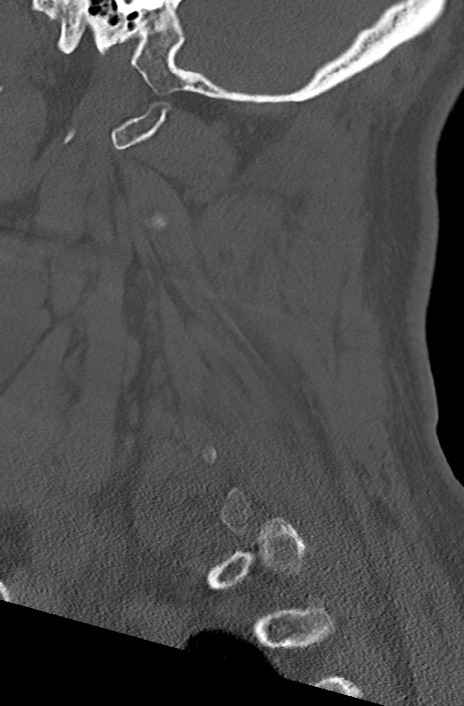

頚椎CT

冠状断像